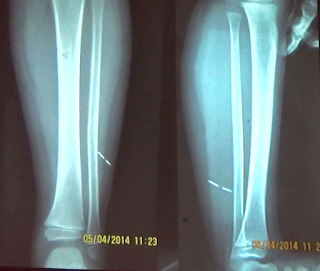

COMPARACION ENTRE UNA FRONTAL Y UNA LATERAL DE

PIERNA

Presencia de un artefacto en las partes blandas de

la pierna

PROYECCION OBLICUA INTERNA

Sirve para evaluar fracturas en los huesos de la pierna.